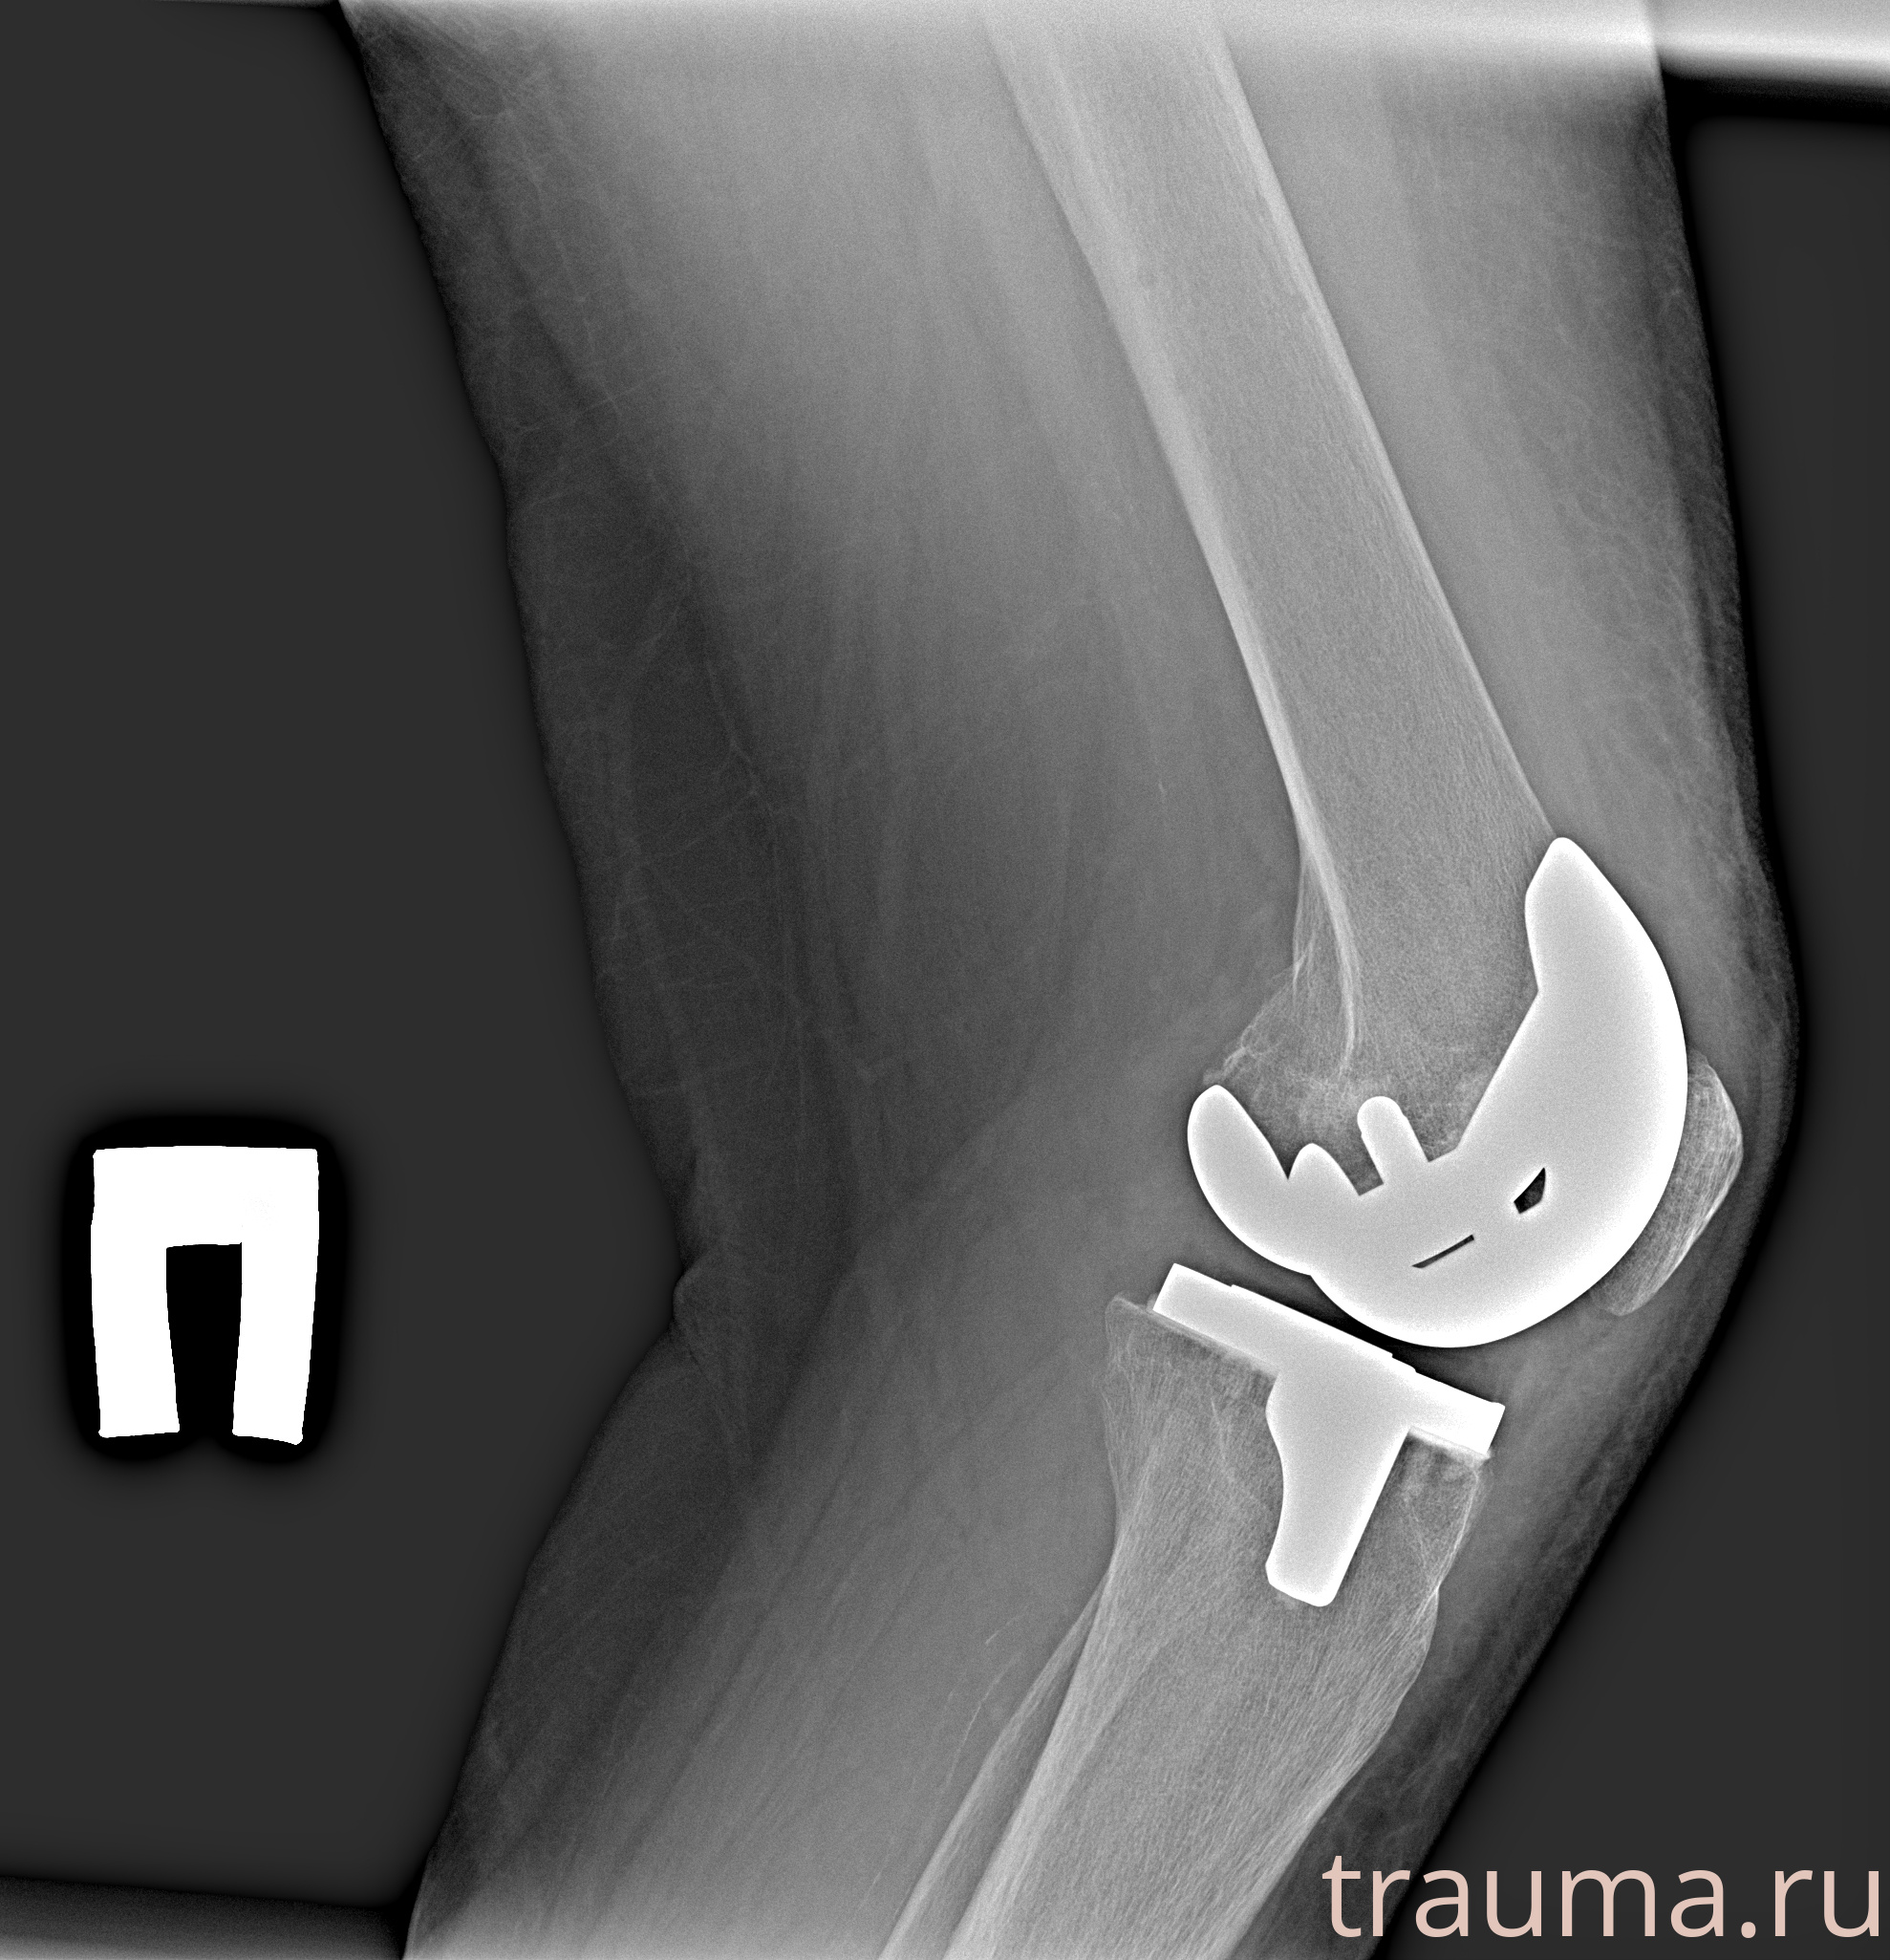

Рентгенограммы

Рентген на дому: по вашему адресу приезжает врач-рентгенолог, травматолог-ортопед с мобильным рентгеновским аппаратом, проводит диагностику травмы или заболевания, делает необходимые рентгенограммы, дает рекомендации по дальнейшему лечению. Получить качественные снимки в домашних условиях возможно благодаря уникальной методике, разработанной МосРентген Центром для института  Склифосовского